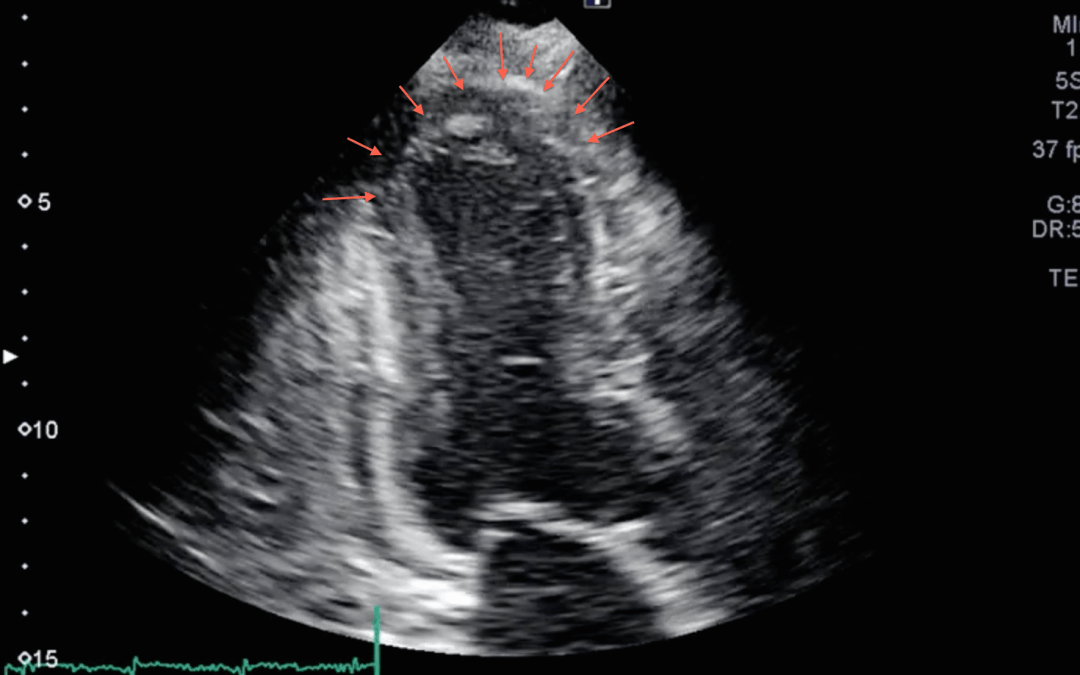

Apical 4-chamber view:

How would you interpret these images?

To the providers taking care of the patient it appeared as though she had a large apical wall motion abnormality. This can be seen best in the Apical 3 and 4-chamber views. Look closely and see how the base of the heart is moving, but it does not appear like the apex is. If this is hard for you to see, cover the apex of the heart with your hand. Look at how the base is moving, and then cover the base of the heart with your hand. See the difference now?

Right ventricular pacing results in an abnormal sequence of activation and so there may appear to be a wall motion abnormality. So the ECG shows no indication of occlusion, but the echo shows a new wall motion abnormality that can be completely due to the pacemaker.

This looks like Takotsubo’s CM / myocardial stunning to me. The apex appears to balloon while the basilar segments of the septum and lateral wall contract.

Really looks ischemic to me. Interested what others think. Seen a lot of V-paced and LBBB Echo images. Usually there’s almost a rolling LV contraction, but all segments will thicken. Here, the apex never thickens throughout the cardiac cycle.

I agree. This looks like many other apical WMAs that I’ve seen which turn out to be secondary to ischemia. It is easy to call this non-ischemic the next day after the patient has had 3 negative trops. The question is what to do with this patient with persistent chest pain, a paced ECG, and this echo at 3AM.